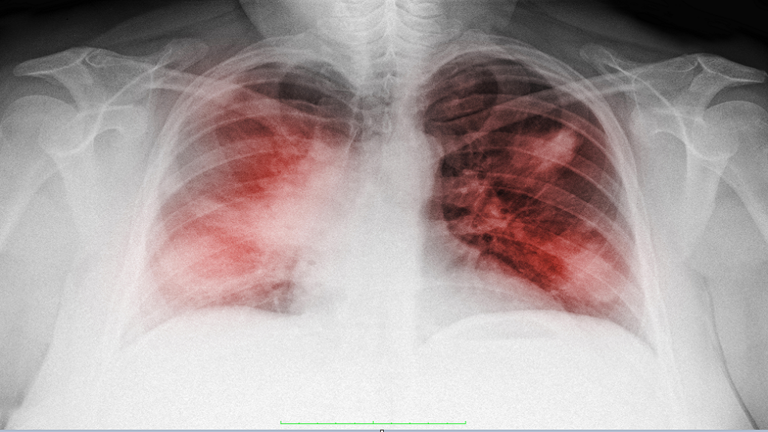

دراسة جديدة تفسر سبب انخفاض مستويات الأكسجين لدى مرضى "كوفيد-19"